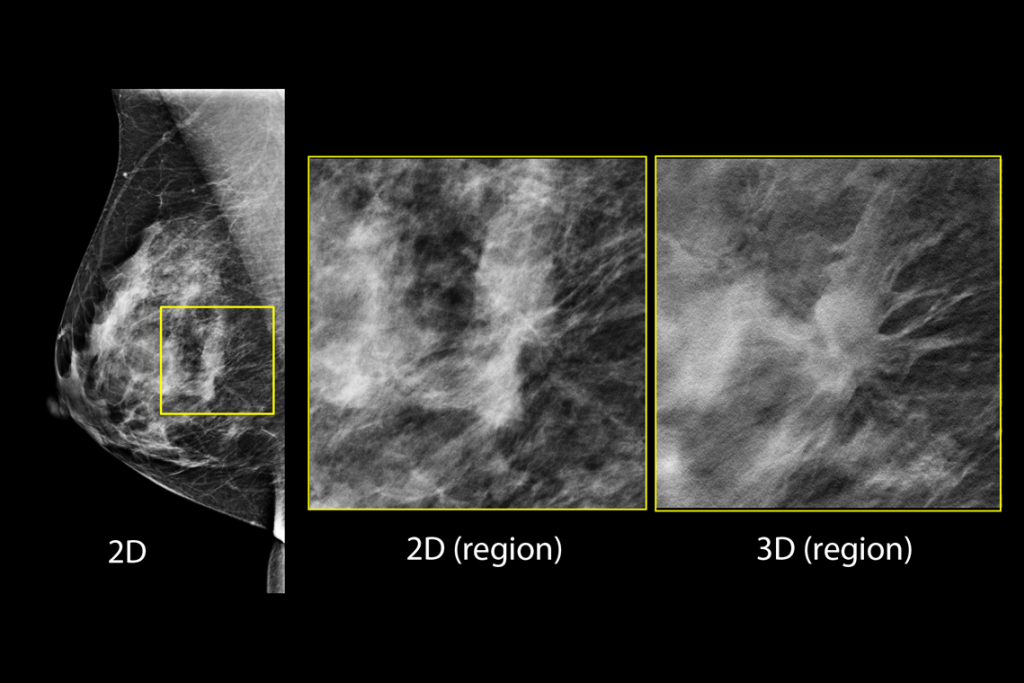

Imagens clínicas de mamografia

Imagens clínicas de mamografia com mama adiposa